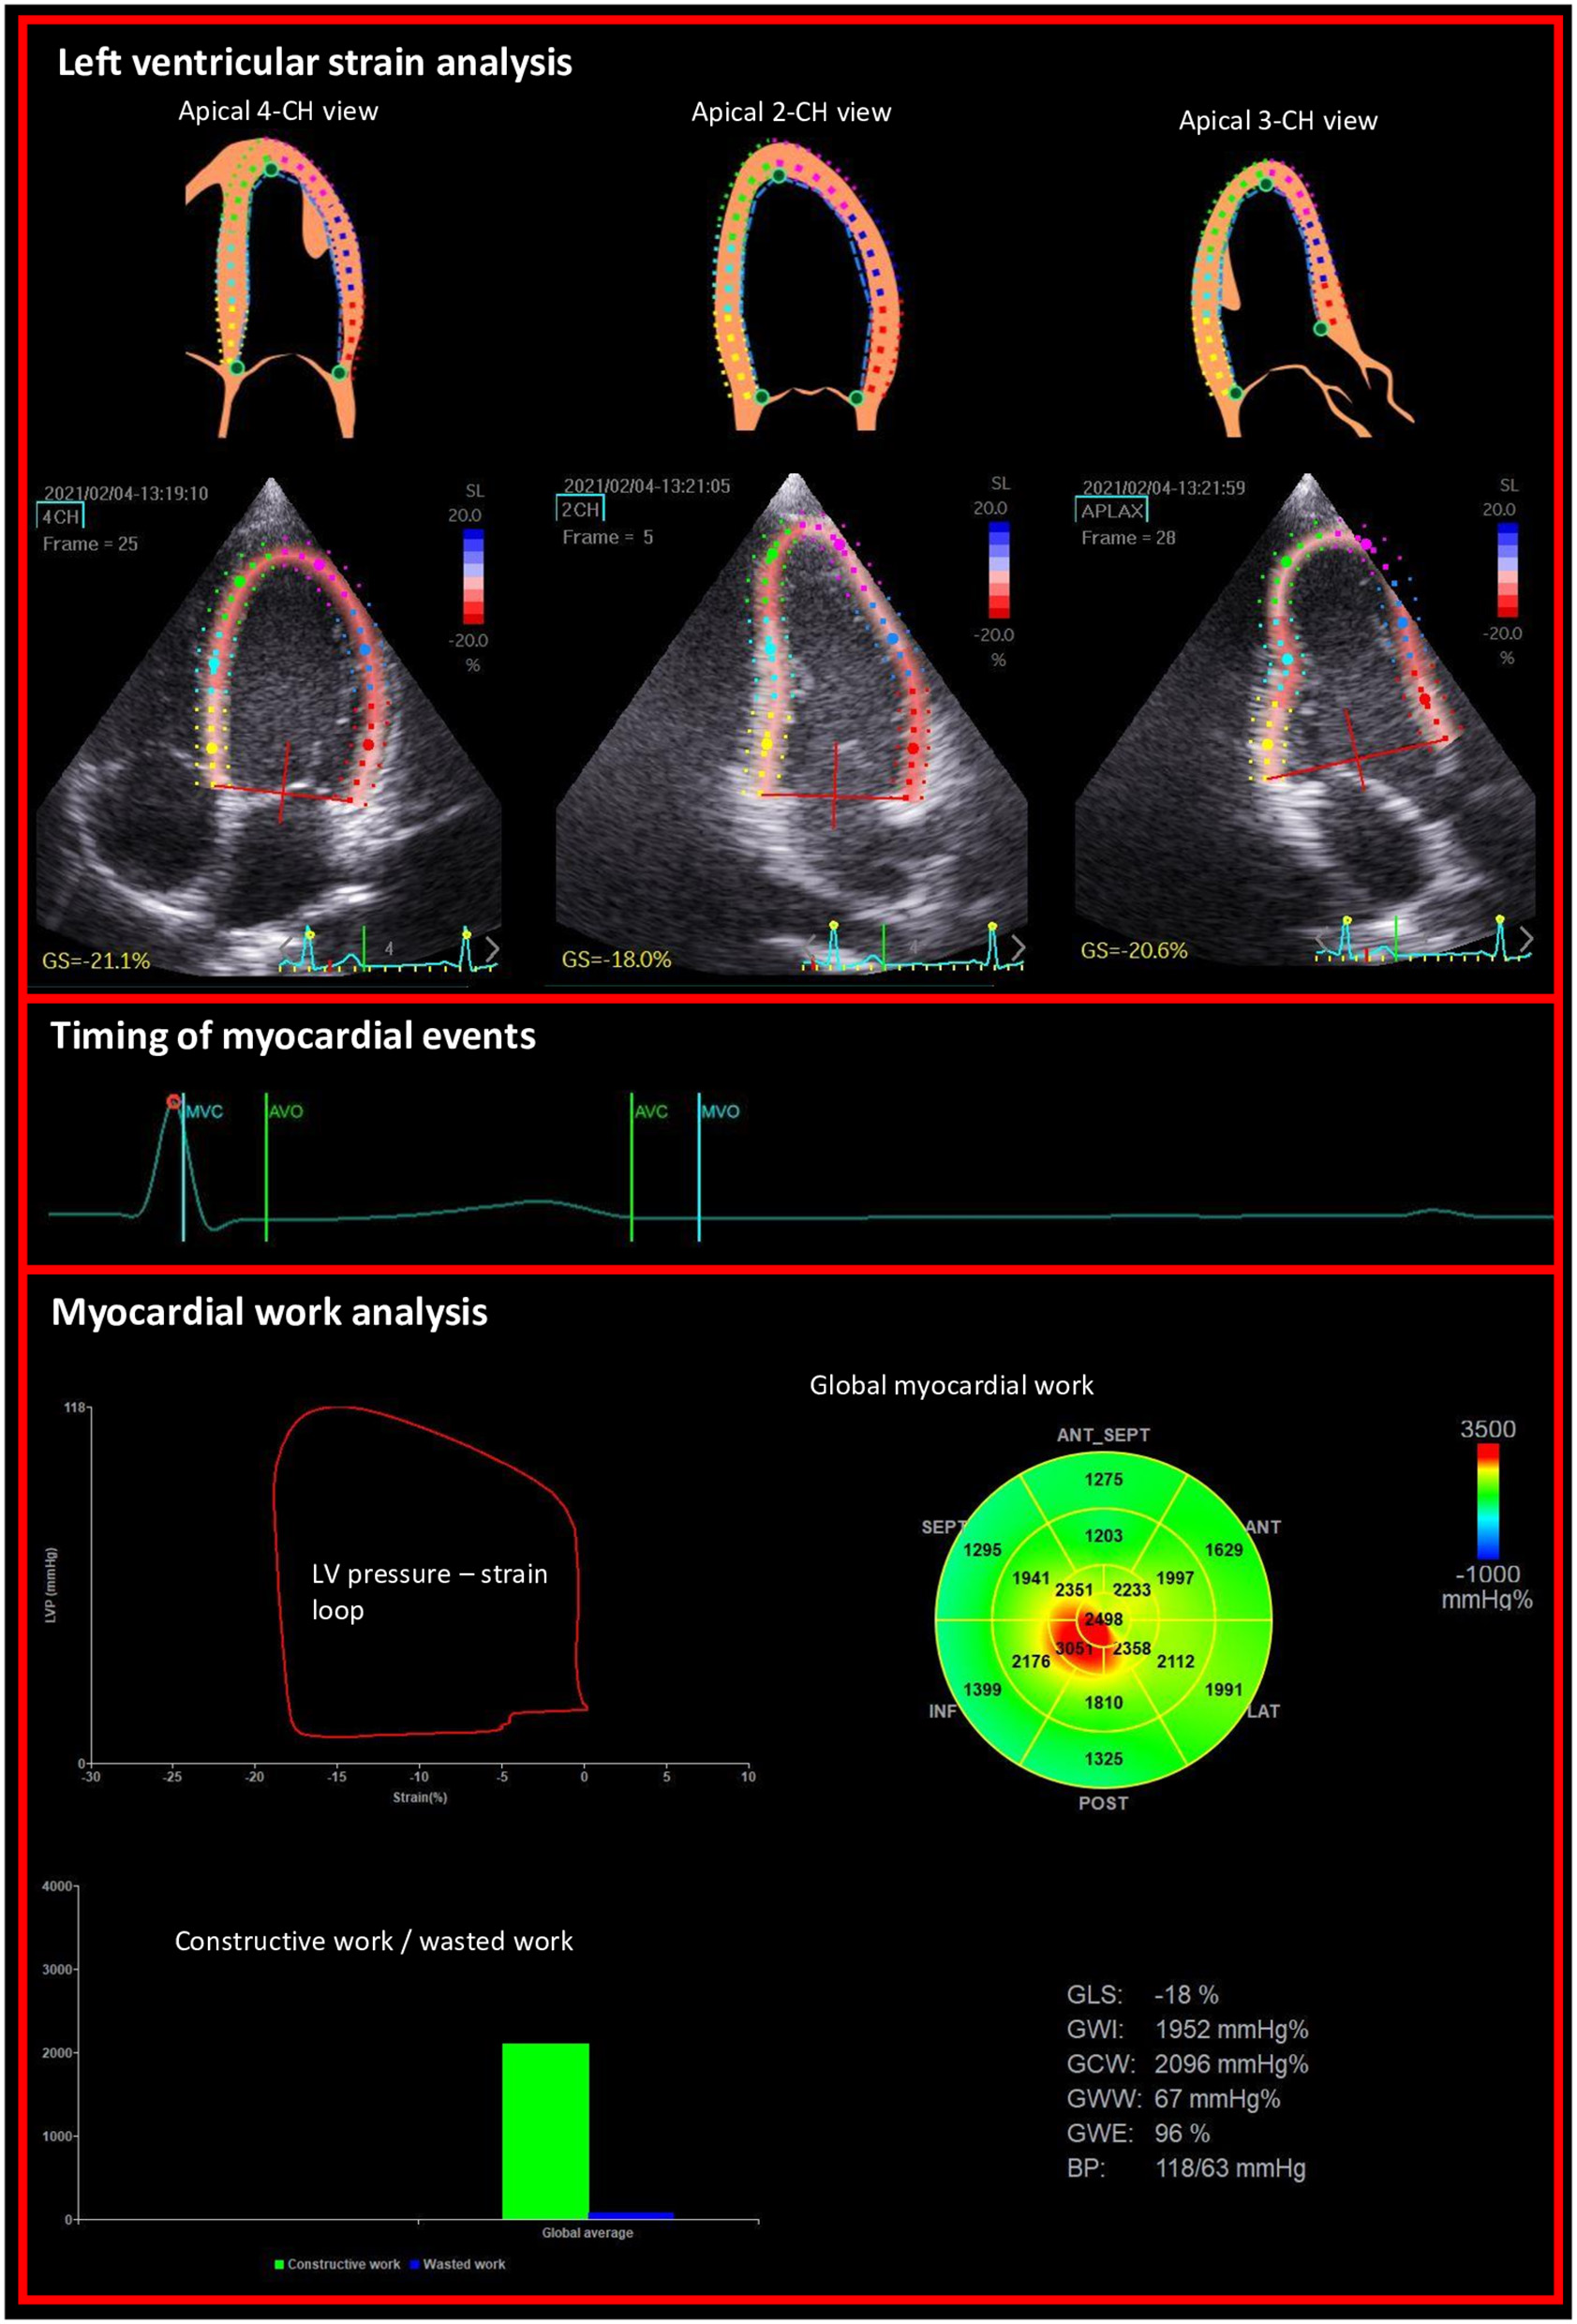

Myocardial work (MW) and related parameters were estimated using the Automatic function imaging of the EchoPac software (Figure 1). MW was estimated as a function of time throughout the cardiac cycle by the combination of LV strain data (recorded on the apical 4, 3 and 2 chambers) obtained by STE and a non-invasively estimated LV pressure curve as described and validated by Russell et al. (7, 8). Peak arterial pressure measured with a cuff-manometer was assumed to be equal to peak systolic and diastolic LV pressures and to be uniform throughout the ventricle. MW was then quantified by calculating the rate of segmental shortening by differentiating the strain curve and multiplying the resulting value by the instantaneous LV pressure.

Figure 1

Example of non-invasive estimation of the LV myocardial work from the left ventricular longitudinal strains on apical views and the timing of mitral and aortic valve events.

MW was calculated from mitral valve closure until mitral valve opening. During LV systole, segmental shortening contributes to the final LV ejection, whereas segmental stretch or lengthening does not contribute to LV ejection. As a result, the work performed by the myocardium during segmental shortening represents MCW, whereas the work performed by the myocardium during stretch or segmental lengthening represents energy loss, which is defined as MWW (9). During isovolumic relaxation, segmental lengthening contributes to LV relaxation, whereas segmental shortening does not. As a result, the work performed by the myocardium during segmental shortening, which does not promote LV relaxation, was considered MWW (9). On the opposite, the work performed by the myocardium during segmental lengthening was considered segmental MCW (9). The global MWE was finally obtained as follow: